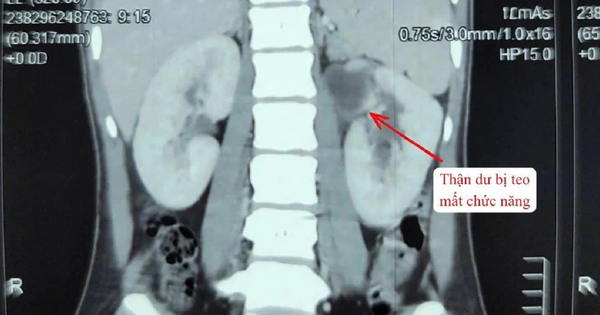

Một phụ nữ 22 tuổi ở Đà Nẵng được bác sĩ phát hiện dị tật bẩm sinh hiếm. Theo các bác sĩ, những trường hợp có 3 quả thận chỉ chiếm 1% dân số. Bệnh có thể gây nhiễm trùng tiết niệu tái phát, tiểu buốt, tiểu rắt, đau vùng hông lưng.